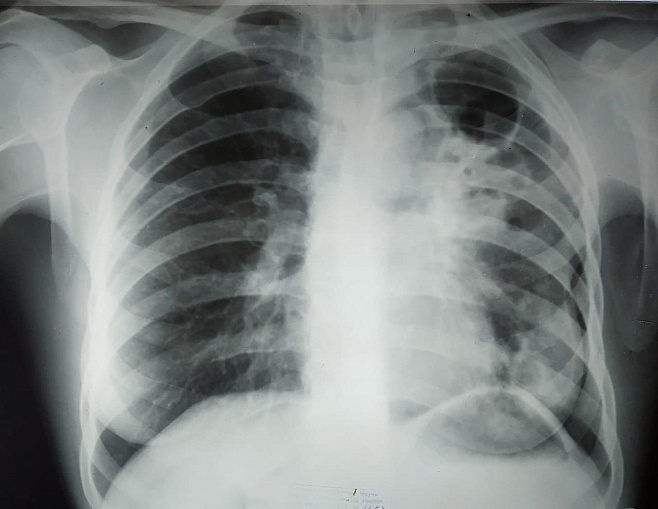

Фото: wiki